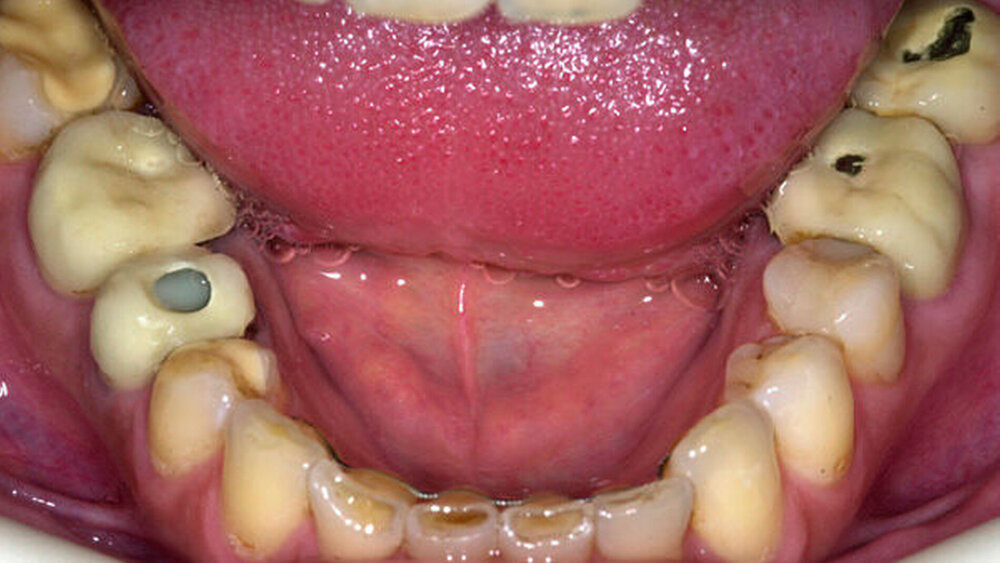

Die Gründe dafür sind verschieden. "Oft ist eine Zahnbehandlung nötig oder das Zahnfleisch hat sich entzündet. Häufig liegt es jedoch auch an nicht funktionsgerechten Prothesen, Brücken oder Kronen“, erläutert Prof. Hans-Christoph Lauer, Leiter des wissenschaftlichen Beirats des KpZ.

Funktionsverluste durch veraltetes Material

Dadurch verändere sich im Laufe der Jahre auch die Kiefersituation. Eine Prothese, die ursprünglich perfekt passte, verliert Lauer zufolge durch Krankheiten oder durch starken Gewichtsverlust ihren Halt. Auchein veraltetes Prothesenmaterial könne zu Funktionsverlusten führen. Daher sei es wichtig, denZahnersatz regelmäßig kontrollieren zu lassen.

Die sogenannte Atrophie spiele ebenfalls eine große Rolle: Geht ein Zahn verloren, bilden sich Zahnfleisch und die Substanz des Kieferknochens zurück. Eine solche Schrumpfung wirke sich ebenfalls negativ auf den Sitz der Zahnprothese aus.